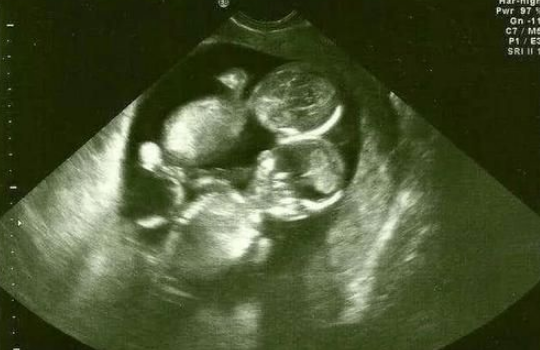

问题描述: 我和老公因为生育方面有问题,所以一直都没能怀上宝宝,于是今年在和家里人商量以后就去做了试管婴儿。医生根据我的情况给我制定了长方案促排,后天正式开始,但是昨天我返院检查身体的时候,给我用了丽申宝注射用尿促卵泡素,想问问大家它的作用是什么?